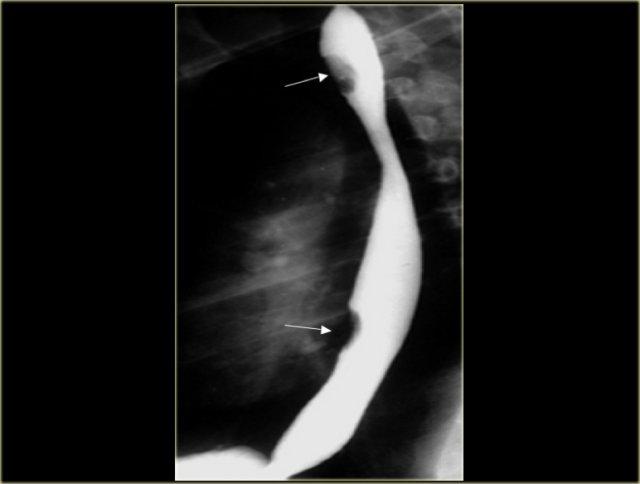

Bên trái là hình ảnh một bệnh nhân bị rách niêm mạc Mallory-Weiss.

Phim chụp điểm cho thấy barium (các mũi tên) trong vết rách niêm mạc dạng tuyến tính gần chỗ nối thực quản – dạ dày.

Vết rách có thể ở thực quản đoạn xa, đáy vị hoặc kéo dài qua chỗ nối thực quản – dạ dày.

Bên trái là hình ảnh một bệnh nhân bị tụ máu thực quản.

Bệnh nhân nhập viện với triệu chứng đau ngực và khó nuốt sau khi nôn mửa.

Ngoài hình ảnh động mạch chủ ngoằn ngoèo, X-quang ngực bình thường.

Chụp thực quản barium cho thấy lòng thực quản hẹp (các mũi tên) trên phim thẳng và lòng thực quản dẹt trên phim nghiêng (các đầu mũi tên), gợi ý tụ máu trong thành thực quản.

Trên CT, chẩn đoán tụ máu trong thành thực quản được xác nhận.

Khối tụ máu thành thực quản tăng tỷ trọng (đầu mũi tên) được thấy cạnh ống thông mũi – dạ dày (mũi tên).

Sau điều trị bảo tồn, sáu tháng sau chụp thực quản barium cho kết quả bình thường.

Bên trái là hình ảnh một bệnh nhân có biến chứng sau nội soi phức tạp.

Can thiệp dụng cụ gây rách niêm mạc và tụ máu trong thành thực quản dạng bóc tách, tạo ra hình ảnh lòng đôi với dải niêm mạc phân tách (các mũi tên).